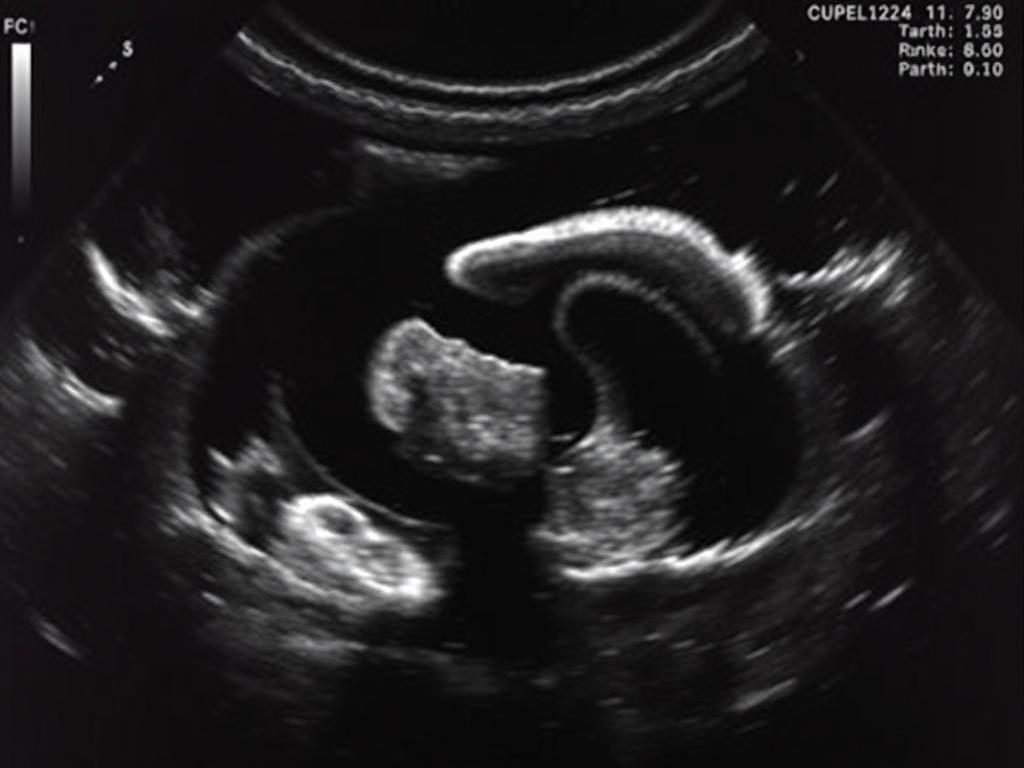

Ультразвуковое исследование (УЗИ) — один из самых доступных, быстрых и безболезненных способов изучить состояние женской репродуктивной системы. Когда речь заходит конкретно о матке и придатках (яичниках и маточных трубах), УЗИ помогает «заглянуть внутрь» без операций и сложных анализов. Это словно получить фотографию того, что происходит внутри, чтобы врач мог понять, что работает как часы, а что требует внимания. Назначают такой скрининг при самых разных ситуациях — от плановых осмотров до обследования при бесплодии, нерегулярных менструациях, болях внизу живота или подозрениях на кисты и миомы. Врач изучает, как выглядит матка, нет ли в ней новообразований, оценит размер и структуру придатков, а также состояние эндометрия — внутреннего слоя матки, который тесно связан с возможностью беременности. Вы можете сделать узи матки и придатков.

УЗИ матки и придатков проводятся двумя основными способами: трансабдоминально (через живот) и трансвагинально (через влагалище). Первый вариант — более привычный и комфортный, особенно если речь о подростках или женщинах с противопоказаниями к трансвагинальному исследованию. Но для подробной картины часто выбирают второй способ — он дает более четкое изображение. Перед исследованием желательно соблюдать несколько правил. Лучше прийти с наполненным мочевым пузырем, если исследование планируется трансабдоминально — это улучшает видимость органов. Трансвагинальное УЗИ выполняется на пустой мочевой пузырь, и тут стоит быть готовой, что ощущения будут немного необычными, но не болезненными. Если вы никогда раньше не делали такое исследование, можно заранее поговорить с врачом и прояснить все нюансы, чтобы снизить тревогу.